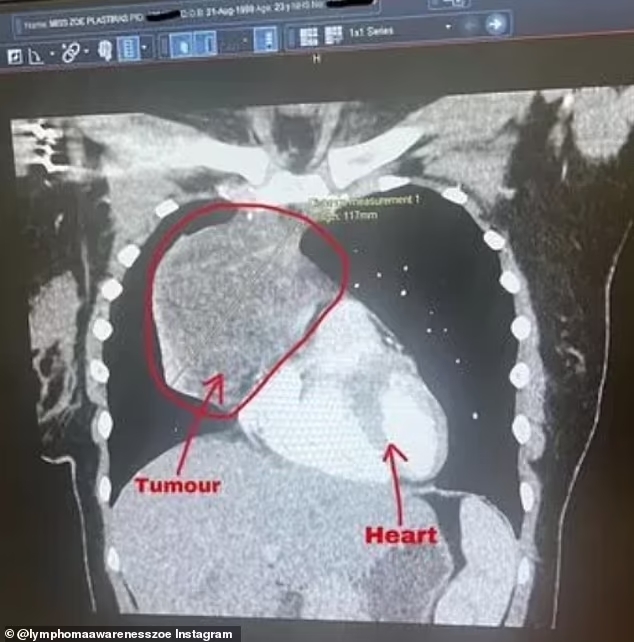

Зои Пластирас била во 32-та недела од бременоста кога лекарите откриле тумор од 12 сантиметри со големина на грејпфрут кој расте покрај нејзиното срце. 23-годишната девојка од Бакингемшир, Велика Британија, била возбудена што ќе стане родител со партнерот Џо Бирд (27), кога нејзиниот свет бил превртен наопаку.

На 10 септември, скенирањето ја открило огромната маса што растела во нејзините гради, што предизвика загриженост.

Зои имала две иглени биопсии кои и двете се покажале како неуспешни, а потоа била примена во болница на 19 декември на хируршка биопсија пред да биде дијагностицирана неколку дена подоцна. Бидејќи масата била канцерогена, лекарите ја отфрлиле идејата за операција на отворени гради и наместо тоа се одлучиле за хемотерапија.

Зои започнала со хемотерапија на 17 јануари до 28 март. За среќа, таа не доживеала никакви „драстични“ симптоми освен опаѓање на косата и го опишала третманот како „брутален“. Туморот се намалил од 12см на 3см, но сè уште била откриена активност на рак во малата преостаната маса. Поради ова таа имала 18 круга на радиотерапија. Потоа требала да чека три месеци за ПЕТ скенирање на 17 октомври.